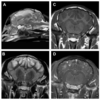

What are the MRI features of a cholesteatoma?

T1w-iso to hypo

T2w- hyper

No CE

No T2* artifact

(Harran, JAAHA 2012)